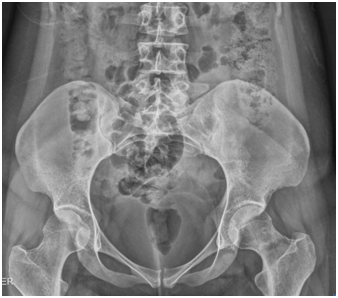

Female patient of 25years-old, active military, size 165cm, weight 52kg, BMI 19.1, with antecedent of military training for about 5 to 6hours a day, 6days a week, for 2months prior to the onset of symptomatology. She refers with discrete right inguinal pain, which increased with physical effort, radiating towards the proximal third of the thigh and right buttock. It is evaluated by a general physician and diagnosed as a muscle contraction, without abnormalities in the x-ray exam (Figure 1) indicating treatment with analgesics and non-steroidal anti-inflammatory drugs, without suspension of physical activities. She comes back to the emergency department of the Naval General Hospital of High Specialty one week later, referring an acute increase in the symptoms and limitation of movement due to pain, an antero posterior pelvic radiograph is performed, without data of apparent bone lesion (Figure 2).

Figure 1 24/08/2015 anteroposterior pelvic radiograph, taken on the day of admission, with no data of apparent bone lesion.